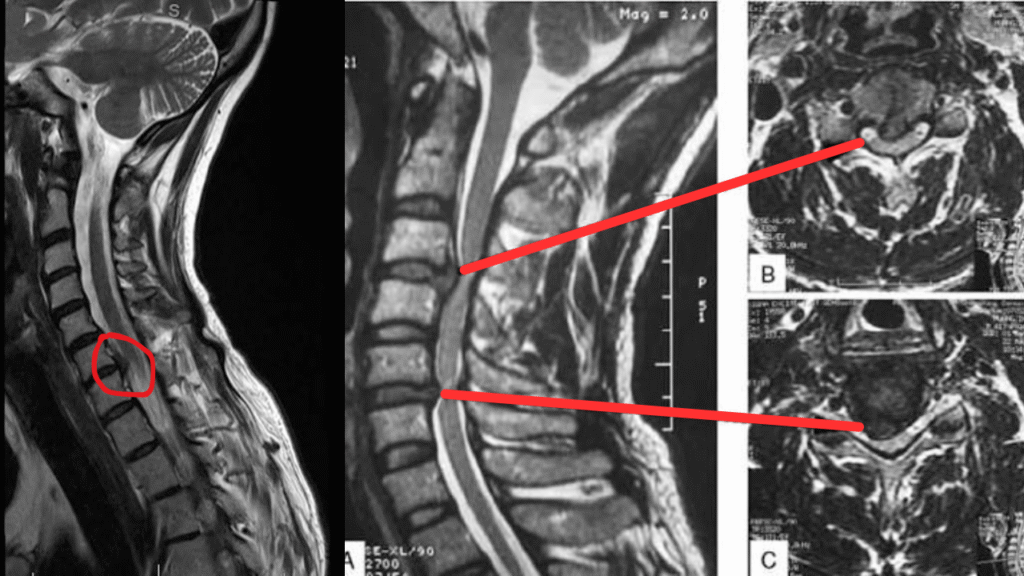

Cervical Disc Herniation MRI

A spine specialist will begin with a detailed physical and neurological examination to assess your symptoms and reflexes. Diagnostic imaging helps confirm the condition and its severity:

• MRI scan The most accurate test to visualize the disc and nerve compression.